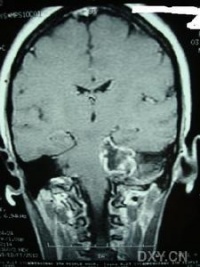

(2)CT及MRI扫描:CT表现为瘤体呈等密度或低密度,少数呈高密度影像。肿瘤多为圆形或不规则形,位于内听道口区,增强效应明显。MRIT1加权像上呈略低或等信号,在T2加权像上呈高信号。第四脑室受压变形,脑干及小脑亦变形移位。注射造影剂后瘤实质部分明显均一强化,囊变区不强化。

(3)CT及MRI检查:目前听神经鞘瘤诊断的标准是Gd-DTDA增强的MRI,特别是当肿瘤很小(<1cm)或在内听道内,CT扫描阴性又高度怀疑肿瘤存在时应该进行GD-DTPA增强的MRI。CT与MRI两种检查有相辅相成的作用,如CT发现有病侧内听道扩大时,增强CT可发现肿瘤对于估计中颅窝入路时颞骨的气化程度及高颈静脉球与后半规管及底的距离有帮助。如果病人已作了CT而肿瘤较大,MRI可提供对脑干压迫的范围Ⅳ脑室是否通畅脑积水、是否存在的情况对可疑听神经鞘瘤或CT检查难于确定时,全序列的MRI可做出鉴别诊断。但也要注意Gd-DTPA的可能假阳性,这与内听道内神经的炎症或蛛网膜炎有关;任何小的接近底部的增强病变应该在六月后作MRI复查,以评估其生长情况。